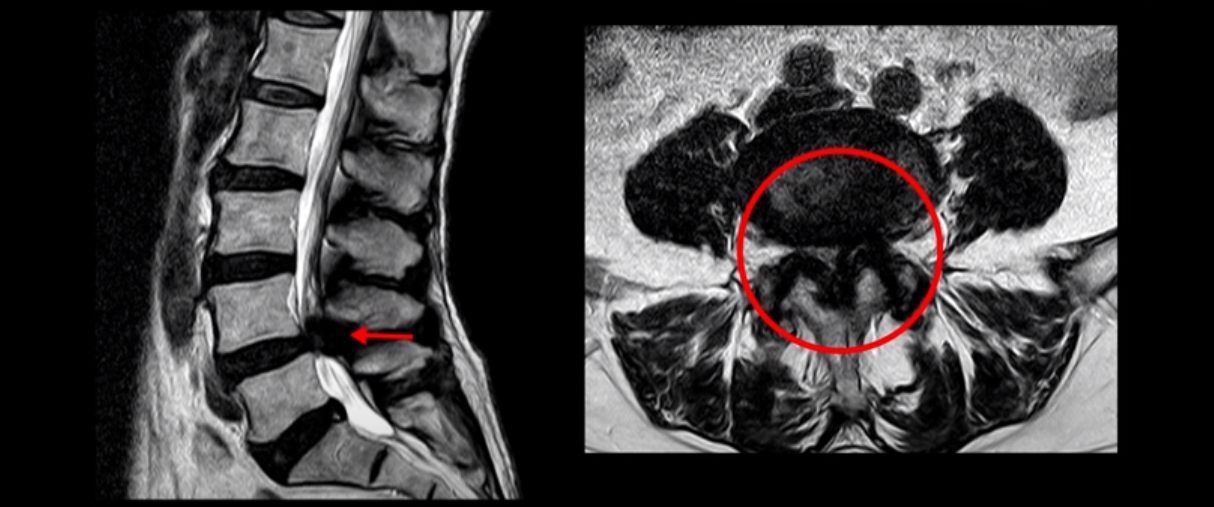

이분 또한 전방전위가 2단계로 매우 심하고, 신경 구멍도 두 마디가 좁아져 있습니다.

전방전위와 협착이 다 심하니까 대학병원에서 나사 6개를 박는 유합술을 권유 받으셨습니다. 그런데 이분이 처음 아프게 된 건 작년 10월인데, 이분이 만약 아프기 전인 작년 초에 MRI를 찍었다면 지금의 MRI와 많이 다를까요? 아닙니다. 거의 차이가 없을 겁니다. 작년 10월에 무리한 일과 운동 때문에 허리 근육에 문제가 생기면서 신경이 눌리기 시작한 겁니다. 만일 아프지 않을 때 MRI를 찍고 신경이 눌렸다고 나사 박는 수술을 하자고 하면, 어떤 사람이 수술을 받을까요?